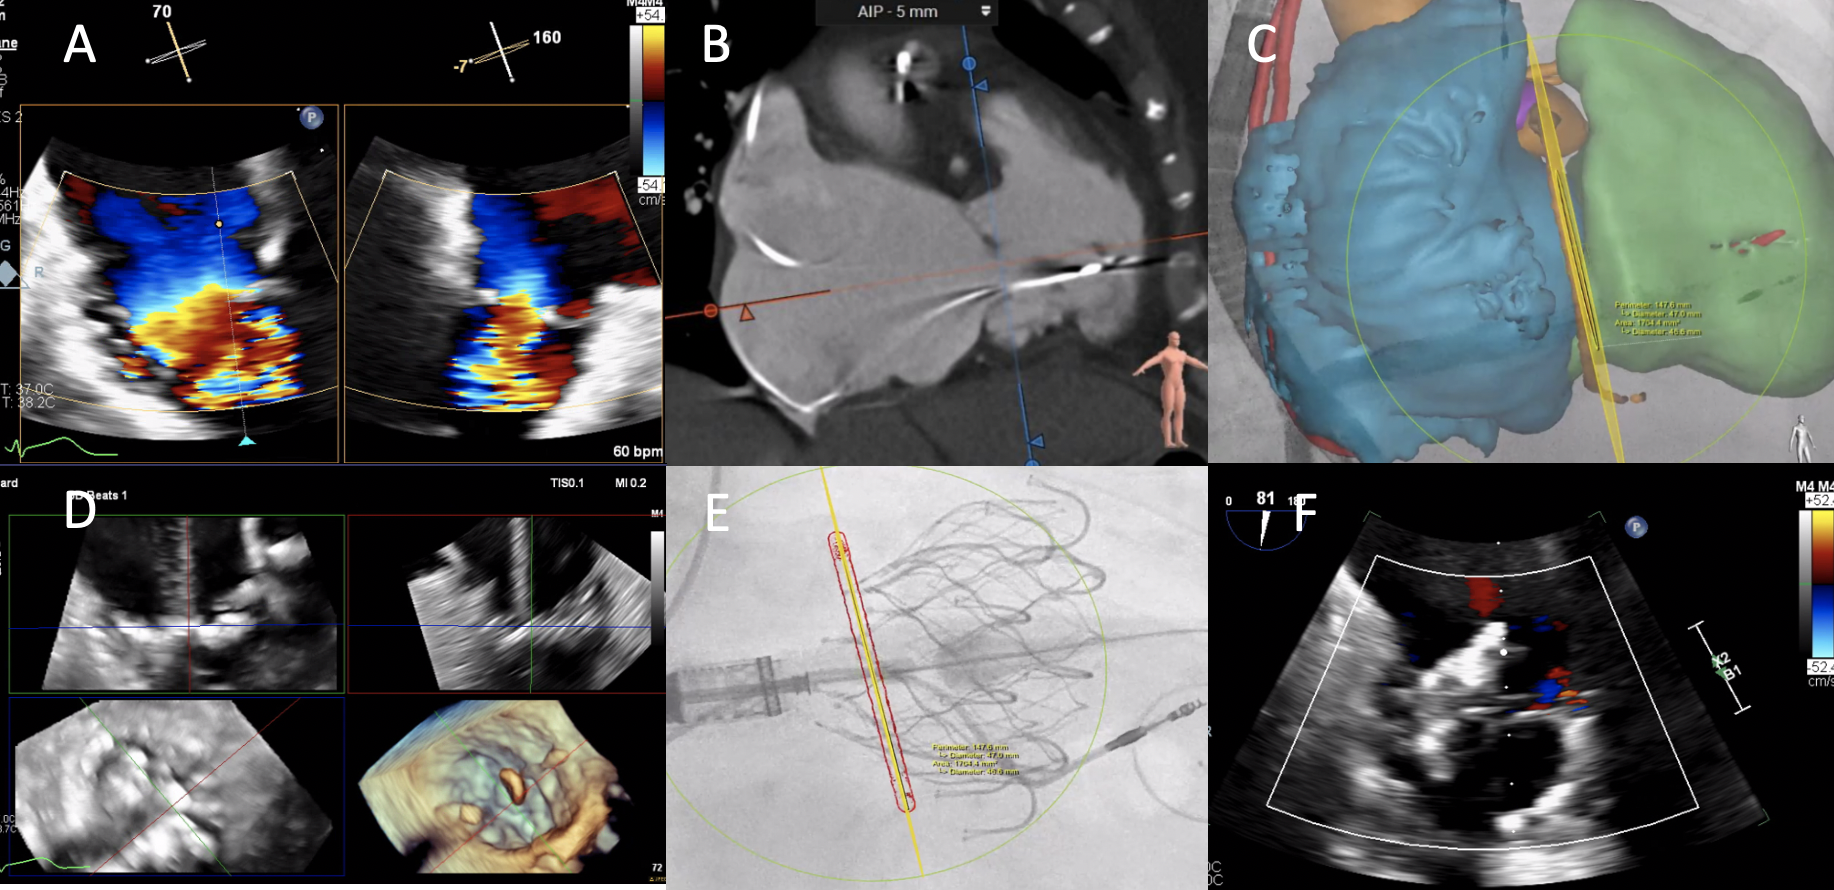

An 82-year-old woman with a history of rheumatic heart disease with mild mitral stenosis and severe tricuspid valve regurgitation/stenosis (Figure A) was referred to our center for transfemoral transcatheter tricuspid valve replacement (TTVR) with the EVOQUE device (Edwards Lifesciences) because of right-sided heart failure symptoms. Preoperative computed tomography (CT) demonstrated thickened tricuspid leaflets (Figure B) with annular sizing suitable for a 48-mm device.

The procedure was performed with transesophageal echocardiography (TEE) and CT-fluoroscopy fusion imaging guidance. The EVOQUE nosecone was advanced across the tricuspid annulus (Figure C) and anchor opening was performed with multiplanar reconstruction imaging guidance (Figure D). After the atrial side of the valve was released, there was slight tilting toward the septal commissure but excellent device function with trace residual intra-valvular leak (Figure E and F; Video). The patient had an uneventful hospital course and significant clinical improvement on follow-up at 6 months.